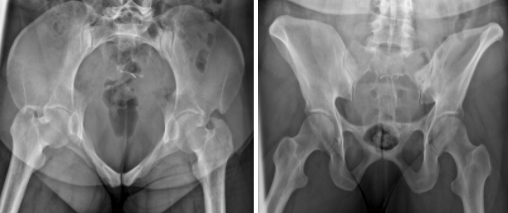

The female pelvis vs male

Female

Wider and more flared

Obtuse angle of pubic arch

Round and large inlet

Male

Narrower, deeper, less flared

Acute angle of pubic arch

Narrow, heart-shaped inlet

In a LPO, how do the hips and obturator foramen appear?

Left hip elongated, right obturator foramen open (criss-cross)

In a RPO, how do the hips and obturator foramen appear?

Right hip elongated, left obturator foramen open (criss-cross)